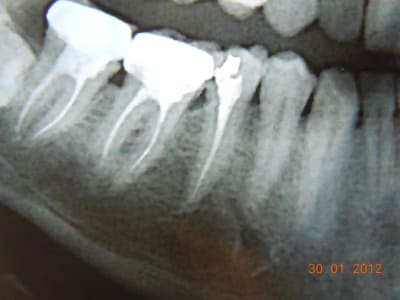

Dscn0753 ahgw2u - Eugenol

Dscn0750 x2wbw9 - Eugenol

Il aurait fallu une photo en vue occlusale. D'après ce que je vois, un joli composite direct doit être largement suffisant. Les prémolaires du bas sont des dents qui se cassent rarement, surtout s'il n'y a qu'une cavité proximale et non MOD (en plus, largement supragingivale)

Il n'y a pas qq chose de louche au mésial de la 47 ?

et comme ceramik, il y a un truc louche sur 47

Refaire aussi la 47 (reprise de carie) et la 46 qui sont dégueulasses.

Pour la 45, un truc sans tenon (soir un compo direct avant de prendre l'empreinte pour 46, soit un inlay).